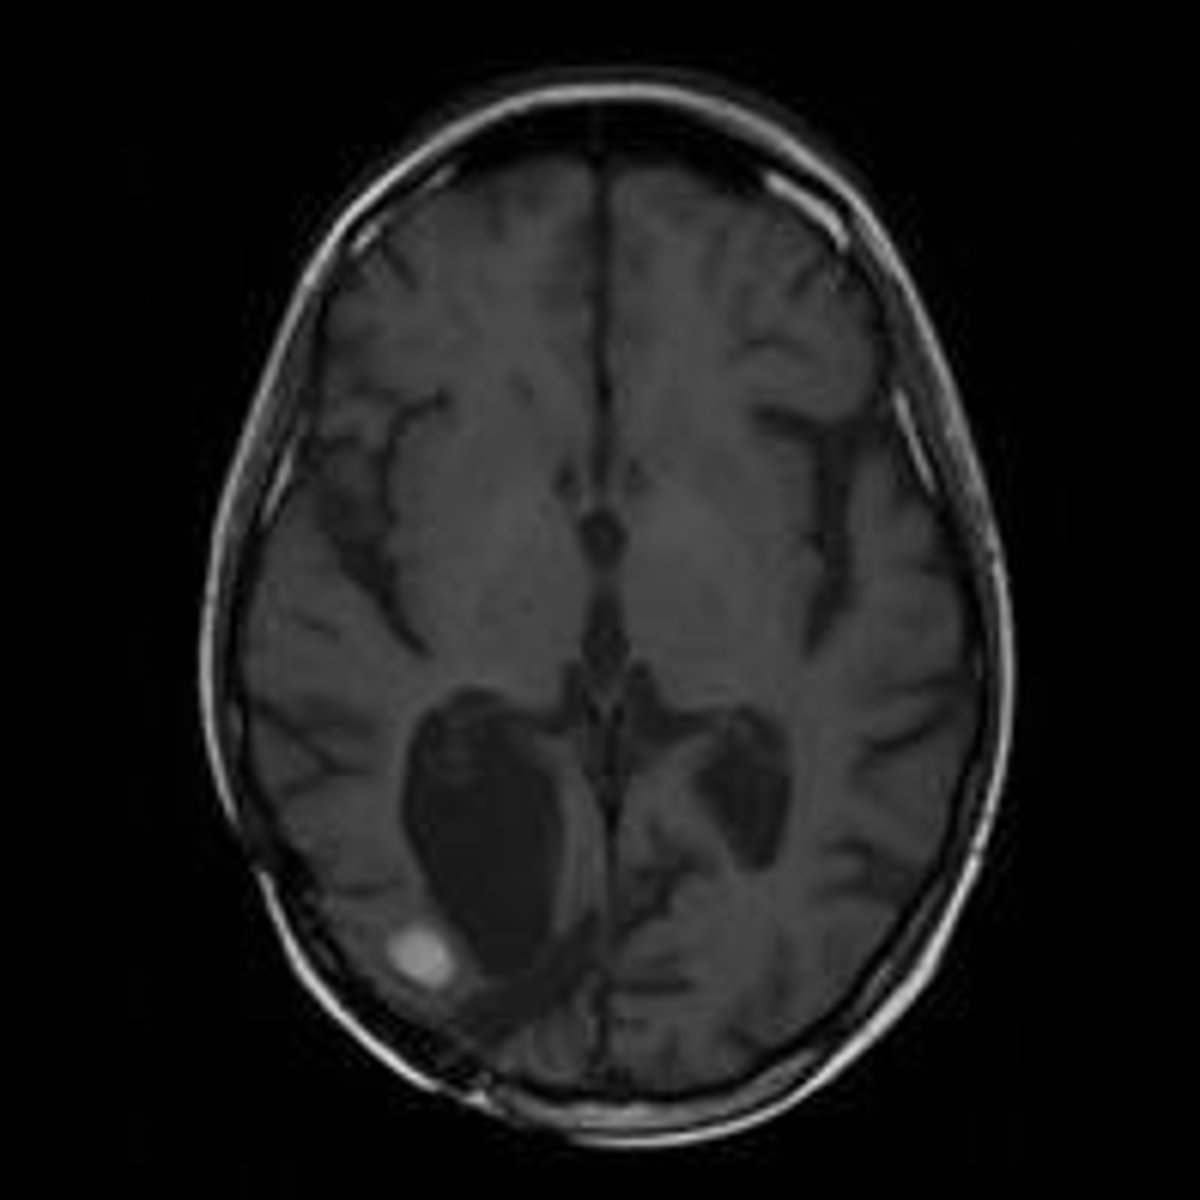

Resonancia Magnética De Un Cerebro Con Metástasis

IDIBELL